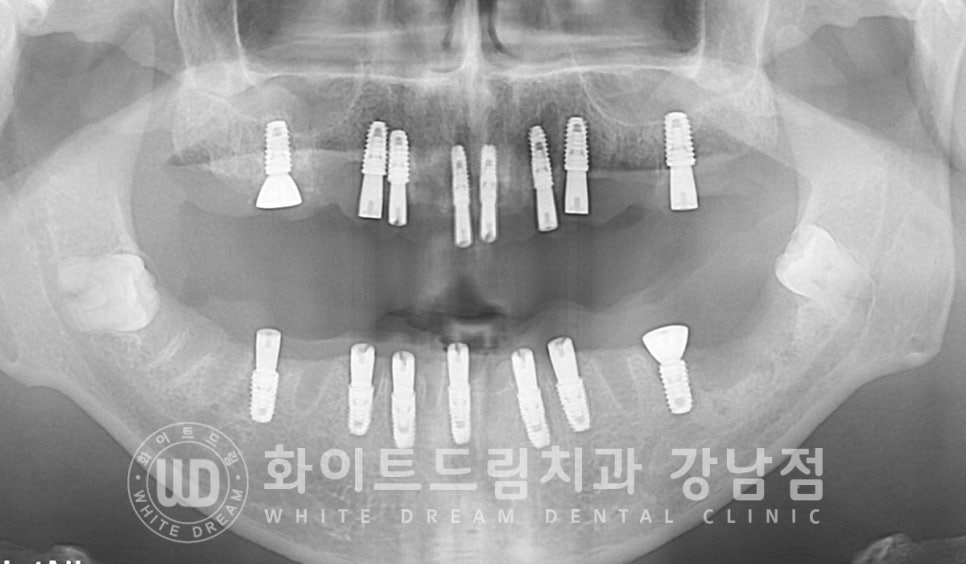

잇몸뼈가 거의 대부분 녹아내려 치아들이 겨우 잇몸뼈에 매달려 있는 상태인데요.

몇몇 치아들은 조금만 치아에 힘을 주면 치아가 바로 뽑힐 수도 있을 정도로

잇몸뼈가 심하게 녹고 치아의 흔들림도 심한 상태였습니다.

28개 자연치아가 모두 있는 상태였으나, 이미 잇몸뼈가 너무 많이 녹아내린 상태여서

손을 쓸 수가 없을 정도였기에 이 모든 치아는 전체 발치를 진행하고

염증으로 잇몸뼈가 많이 소실된 부위는 뼈이식을 동반하여 임플란트 치료를 진행하기로 했습니다.

▲ 상악 임플란트 전체 식립 & GBR : 24.01.11

상악은 16번 임플란트 식립 부위의 상악동 거상술을 진행했고

상/하악 모두 염증으로 소실이 심했던 부위는 뼈이식(GBR)을 동반하여 수술을 진행하였습니다.

▲ 하악 임플란트 전체 식립 & GBR : 24.01.18